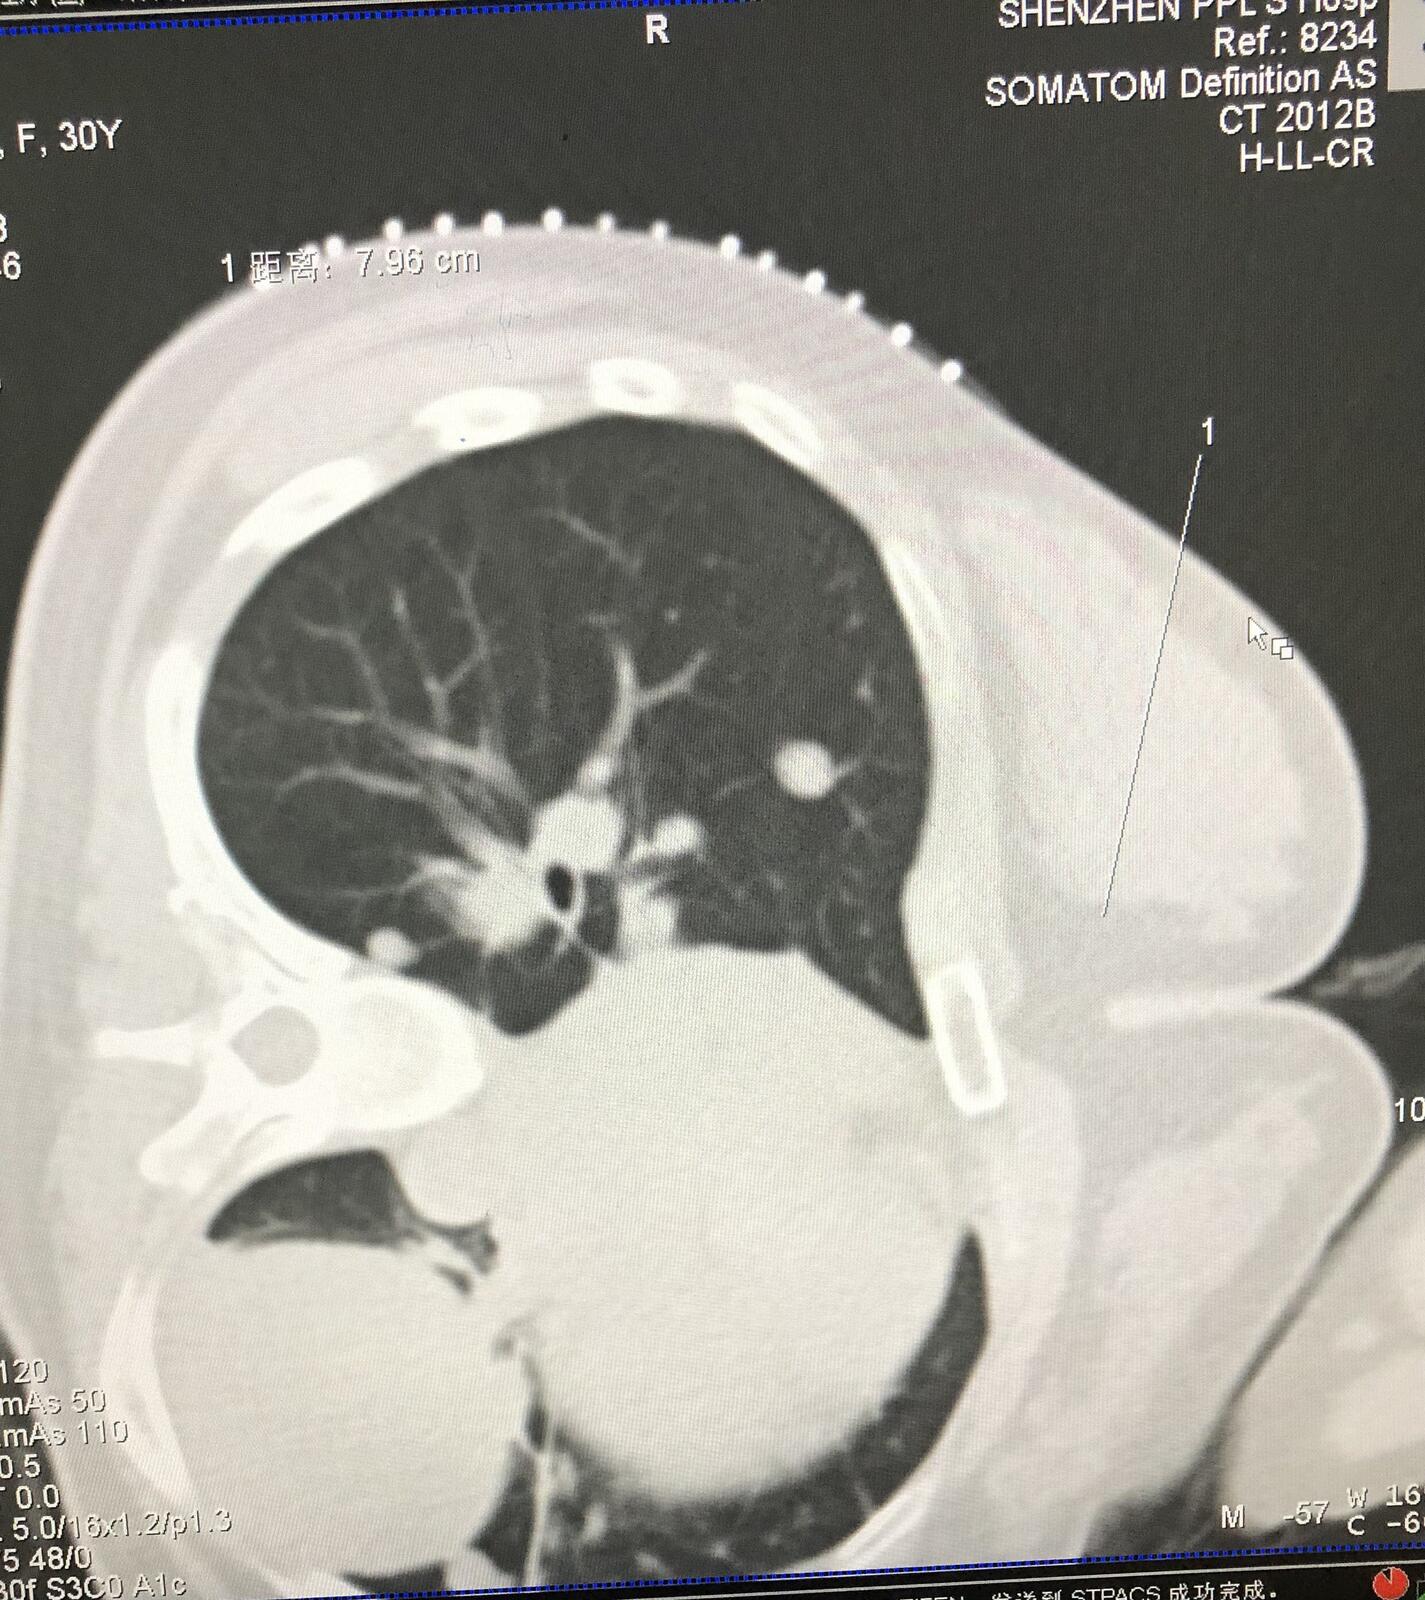

2.患者女性31岁,腺泡状软组织肉瘤术后肺转移,行微波消融治疗。

右肺转移瘤直径约1.3厘米,患者侧卧位。

见微波消融针穿刺病灶并就行消融治疗。